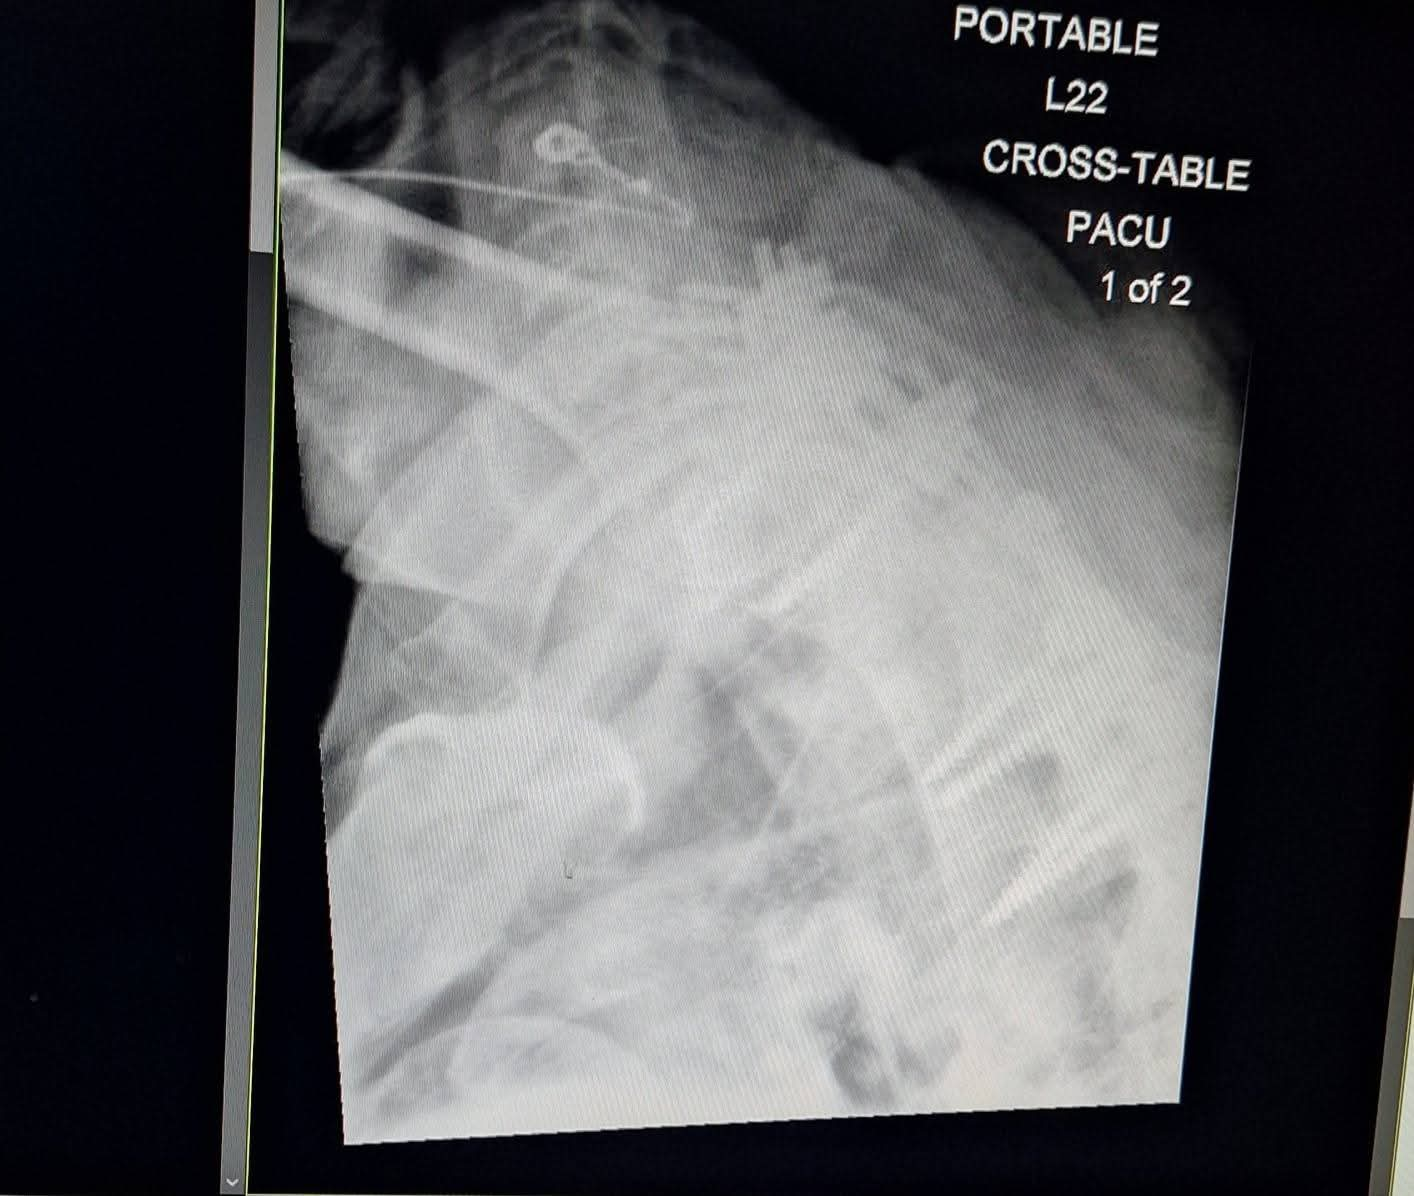

We are reaching out with heavy hearts and unwavering faith as Terry faces Metastatic Renal Cell Carcinoma, an aggressive form of kidney cancer that has already spread beyond the kidney. Terry is currently recovering from thoracic spine surgery where the surgeon fused C5-7 and rebuilt around T1, 2, and 3. This surgery was performed to de-bulk a lemon-sized tumor that was choking out his spinal cord and causing severe bone damage. From recent scans (7/21), we learned that the tumor is still very large and has potentially grown since surgery.